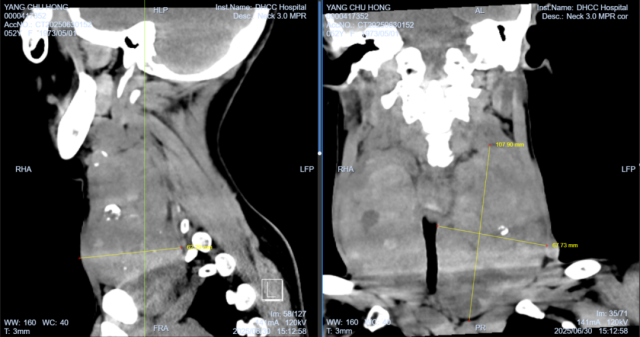

颈部近10X15厘米的巨大甲状腺肿物影像图片

接诊的颈胸外科邓江波主任医师团队详细检查评估后,刘女士诊断为“巨大甲状腺合并继发甲亢”,甲状腺已肿大如“巨大的苹果”,严重压迫气管,“若任其发展,窒息风险极高,手术切除是根治的较好选择。”邓主任介绍。

尽管该团队在粤北地区率先开展并精通腔镜甲状腺微创手术,但考虑到肿物体积巨大、与气管、血管、喉返神经等重要结构粘连紧密、手术空间受限等因素,腔镜手术风险显著增加。而且患者合并甲亢,手术难度极大,有出血较多的风险。经过严谨评估,团队决定采用更为稳妥、视野更佳的传统开放手术方案,以确保安全彻底地切除病灶。